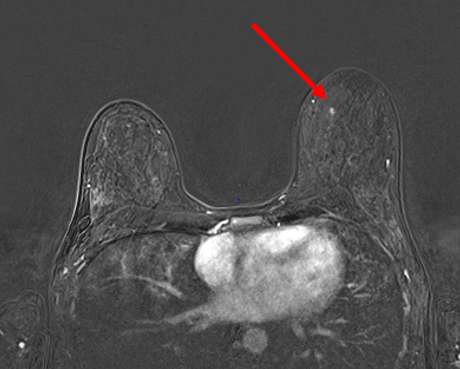

Focus is defined by BI-RADS as abnormal enhancement measuring less than 5mm in diameter that is too small to characterize and cannot be categorized as a mass or non-mass enhancement (1) (Figure 1). Abnormal enhancement describes an area that enhances above the background parenchymal enhancement on contrast-enhanced MRI sequences (2). Kinetics are a useful adjunct in breast MRI for further characterizing enhancing lesions, however, the small size of foci (< 5 mm) may limit kinetic analysis due to partial volume averaging. Partial volume averaging is a phenomenon that occurs when a lesion is below the resolution of the imaging modality.

Why are foci important in breast MRI? Because they can be malignant (3). Reports in the literature provide a very broad range of estimated risk of malignancy (3-6%), therefore, these findings are often characterized as BI-RADS 3 – likely benign and short-term follow-up is recommended. In the event that a focus increases in size, is new, or demonstrates washout kinetics, then it could be assigned a BI-RADS 4 – suspicious – and a biopsy (likely MR-guided biopsy) would be warranted. In some cases, enhancing foci may be categorized as BI-RADS 2 – benign – if they have features specific to benign lesions (i.e. cyst, fat necrosis, lymph node, apocrine metaplasia, and myxoid fibroadenoma).